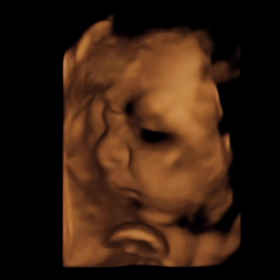

• 産まれましたの画像

産まれました